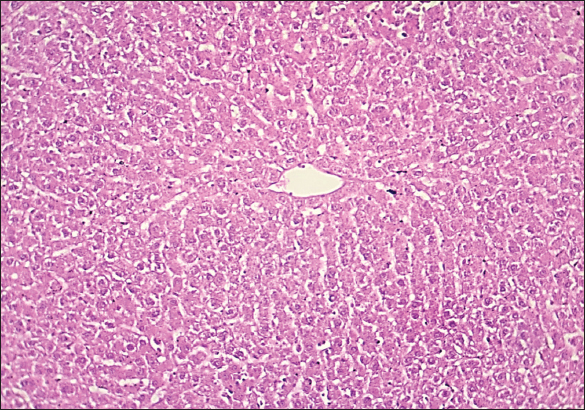

Fig. 3. Histological section of liver in rats drenched with 0.6 mg/kg citalopram and treated with 20 mg/ kg J. regia pulp extract. The section shows the normal histological structure of hepatic tissue without any significant occupied lesion (H and E stain 100X).